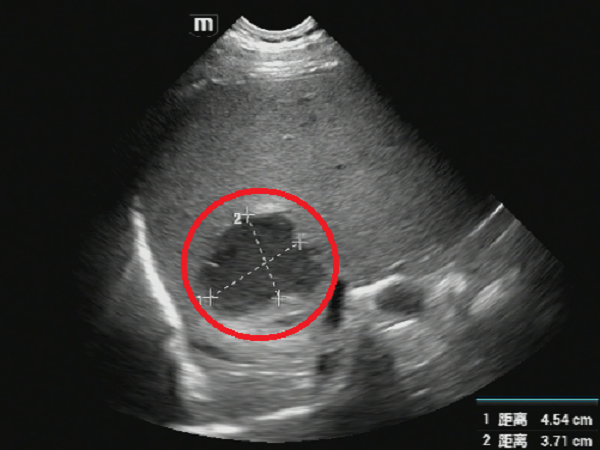

超声所见:肝多发脓肿,其中已完全液化较大者位于右肝前叶上段(图1),故拟行经皮右肝前叶上段脓肿穿刺置管引流术。

图1 红色圆圈处为肝脓肿